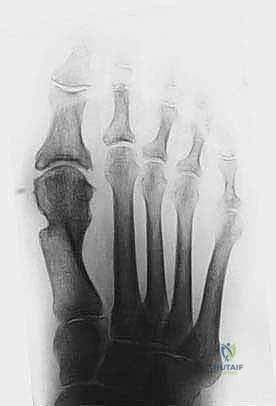

Operative Techniques in Orthopaedic Surgery